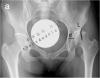

陈晓东教授提供—双侧髋臼发育不良

病情概述: 患者,男性,22岁。双侧髋臼发育不良。长时间行走后,右侧髋部出现疼痛。接受髋臼周围截骨手术后,髋臼对股骨头的覆盖恢复正常。 [详情]